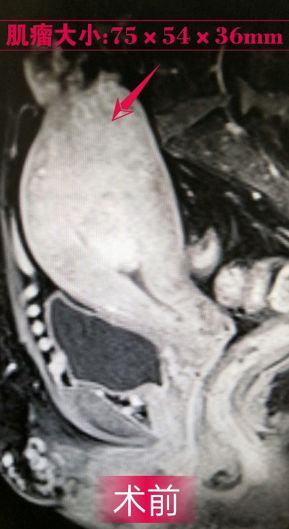

38岁,每次“大姨妈”驾到,腹痛难忍,还逐渐出现便秘,大便不畅等压迫症状,患者不愿切除子宫,进行子宫动脉栓塞术。 诊断为:子宫腺肌瘤